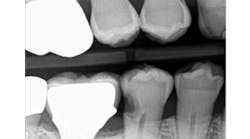

When decay arises on adjacent teeth, dentists must evaluate their treatment options. I have found there is a high degree of difficulty restoring large Class II or interproximal lesions with direct composites, especially when the decay is on premolars. It is much more predictable to restore Class IIs on molars with tight contacts, but it can still be difficult. I have tried full matrix bands and multiple sectional matrix bands, but I can’t create a nice contour with a tight contact. I have even tried traditional composites and bulk fill without great success. See Figures 1 and 2 showing my open contacts with direct composite.